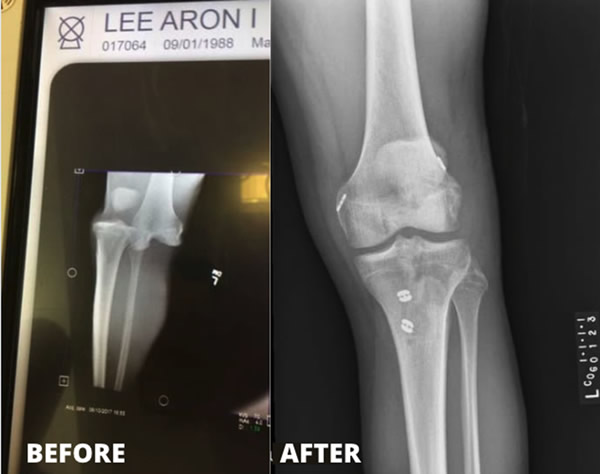

In 2017, Aron Lee was playing in a competitive slow-pitch softball tournament and experienced a terrible knee injury.

An MRI of Aron's knee was performed in order to see the extent of the damage to the ligaments and tendons. The MRI demonstrated that he had suffered complete tears of the Anterior Cruciate ligament, (the ACL), The Posterior Cruciate ligament, (the PCL), and the Lateral Collateral ligament (the LCL). The ACL and PCL cross each other in the middle of the knee. They each attach to the femur and tibia and help to hold the bones in proper position relative to each other. The LCL attaches the femur to the tibia on the outer side of the knee and also helps to hold the bones in their proper positions. The MRI also showed a small fracture of the tibia.

Aron eventually had surgery by Dr. Yehyawi to repair the ruptured ligaments.

"It was a long road of recovery because my injury happened in June of 2017, and I had to go through physical therapy before I could even have surgery. Even though the surgery was scheduled for August 2017, Dr. Yehyawi wanted more time for improvement on my flexion before going through surgery. He was always looking out for my best interest. I had my surgery in September 2017 which included complete reconstruction of the ACL, PCL, and LCL with donor hamstring tendon, and the surgery lasted a long time! With continued physical therapy visits 2-3 days a week and visits with Dr. Yehyawi, I was able to walk out of COG fully recovered on August 10, 2018."